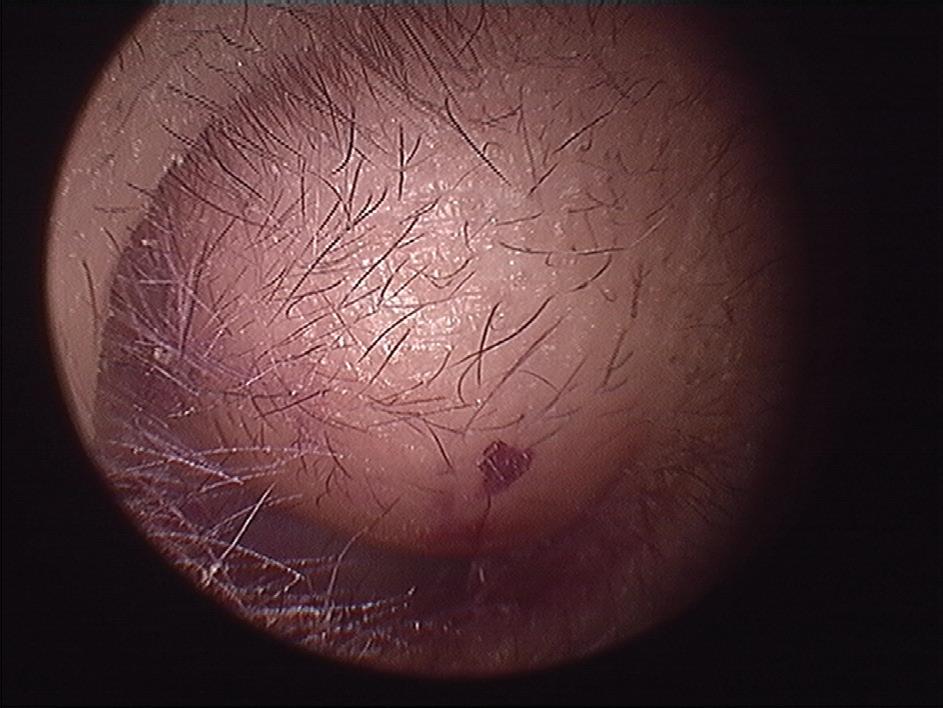

Iatrogenic external auditory canal cholesteatoma with mastoid erosion

A 70-year-old man who had undergone postauricular underlay myringoplasty to treat chronic otitis media 10 years earlier presented with a 6-month history of hearing impairment, aural fullness, and occasional otorrhea of the right ear. Otoscopy revealed a large, bulging mass on the posterosuperior aspect of the external auditory canal (EAC); the tympanic membrane was invisible (figure 1). Computed tomography of the temporal bone revealed a right-sided, 2 × 2-cm soft-tissue mass in the EAC, with erosion of mastoid air cells but a normal eardrum and middle ear cavity.

Considering the postsurgical history and the site of the mass, we diagnosed an iatrogenic EAC cholesteatoma. A whitish, spherical mass was identified on surgical exploration and was completely removed through the prior postauricular incision (figure 2). We subsequently performed canalplasty with EAC

defect reconstruction using fragments of conchal cartilage. The pathologist’s report revealed histopathologic features compatible with cholesteatoma. No evidence of recurrent disease was present during the 5-year follow-up.

Iatrogenic EAC cholesteatoma is a rare complication developing after myringoplasty. The precise incidence of the disease remains unknown. We speculate that inversion or malpositioning of a tympanomeatal flap, or unintentional implantation of epithelium during the prior surgery, causes the subsequent defect.1,2

Figure 1. Otoscopy displays a large, bulging mass in the posterosuperior aspect of the external auditory canal.